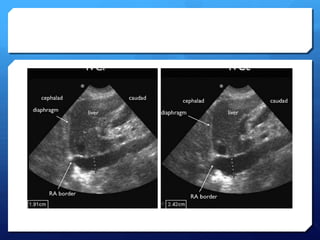

Tamponade using ultrasound

 A moderate-large effusion.

 Right atrial collapse

 Atrial contractionnormal in atrial systole

 Collapse throughout diastole or inversion is abnormal.

 RV collapse during diastole when meant to be filling

(‘scalloping’ seen)

 Whats seen in the IVC…

Tamponade using ultrasound A moderate-large effusion.  Right atrial collapse  Atrial contractionnormal in atrial systole  Collapse throughout diastole or inversion is abnormal.  RV collapse during diastole when meant to be filling (‘scalloping’ seen)  Whats seen in the IVC…

American society ofEchocardiography 2010 guidelines